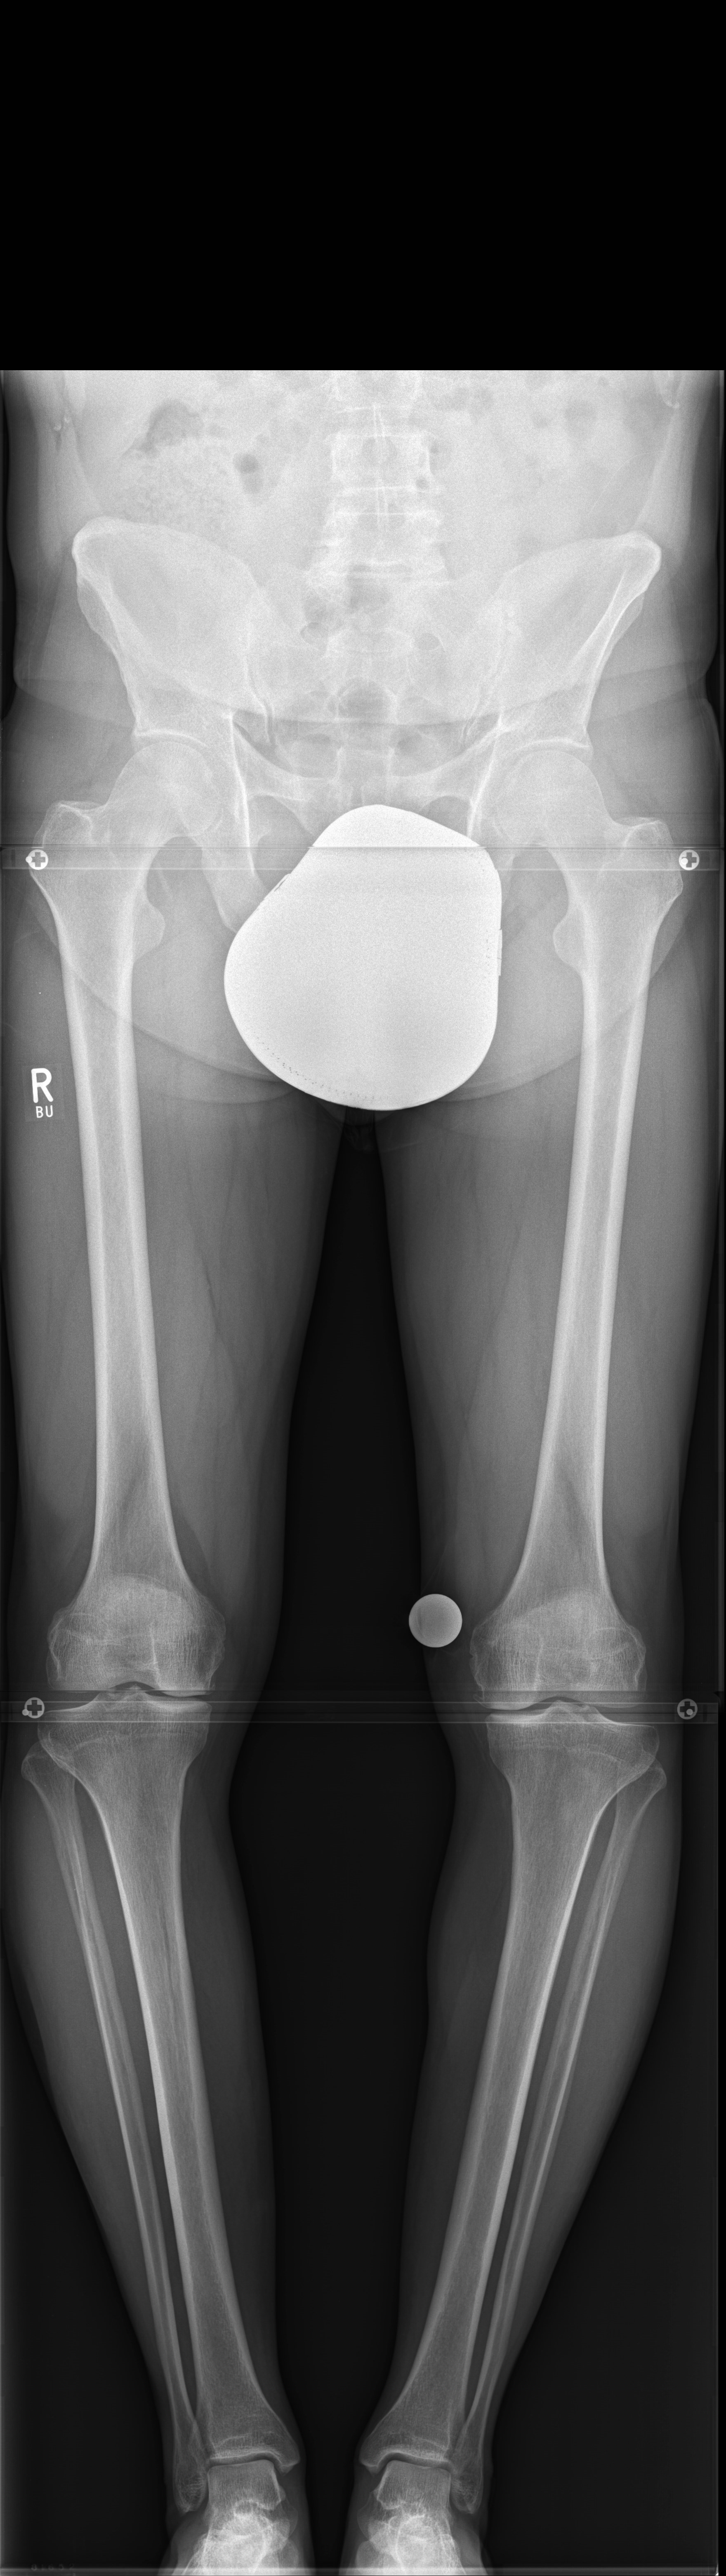

Case 1

(Case provided by Stefan Schröter)

A 33-year-old woman complained of pain in the lateral compartment after a normal working day. Sports activities were no longer possible. Free range of motion (ROM: 0/0/150°), ligaments in sagittal, and coronal planes were stable. There was no effusion. The patient had valgus deformity which was corrected with a distal femoral osteotomy.